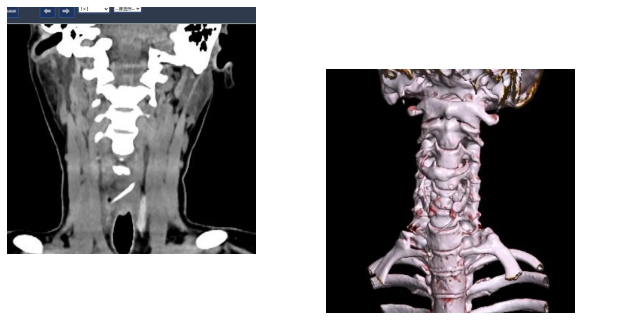

接诊的吕主任详细询问了陈女士的情况,结合她持续加重的咽痛,判断事情没那么简单。立即安排她进行双源CT检查并辅以三维重建技术。检查结果让所有人都捏了一把汗:一根近3公分长的鱼刺,深深卡在食管入口处,不仅位置刁钻,还已经刺穿食道,周围创面出现感染。

消化内镜室迅速启动取刺准备,当胃镜缓缓抵达食管入口时,清晰可见一根长约3cm的鱼刺,正斜斜嵌顿在食管入口的右侧壁,鱼刺尖端已刺入黏膜下层,周围黏膜因刺激出现明显充血水肿。更棘手的是,鱼刺恰好卡在食管入口的生理拐弯处,这个部位是食管与咽喉的衔接点,角度刁钻,内镜难以稳定固定位置。